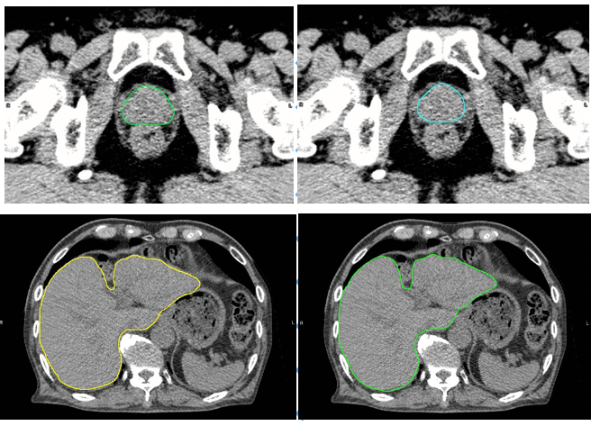

ひょうご粒子線メディカルサポートは2019年からNVIDIAが提供する事前学習済みモデルや既存のモデルのアーキテクチャをベースとし、腫瘍と周辺正常臓器輪郭を作成する各種AIモデルの作成、およびトレーニングを NVIDIAのDGXシステムで行った。学習データには兵庫県立粒子線医療センターと大阪大学医学部附属病院の実際に治療した1,500症例以上の計画画像、および放射線治療専門家によって抽出された輪郭データを用いており、これにより頭頚部、胸部、腹部、骨盤部の主要臓器を自動で作成するモデルを兵庫県立粒子線医療センターや大阪大学大学院医学系研究科の研究グループらと共に開発している。

肝臓モデルを使用した例では、輪郭作成に要する時間は、従来の手作業のみでは30分以上要したものが、臨床利用ための人による修正時間も含め、Ai-Segによる自動輪郭作成及び必要に応じての軽微な修正作業を合わせて5分程度までに短縮することができた。図1に示すように医師とAi-Segが作成した輪郭を比較しても違いがわからないほどの水準にまで達している。